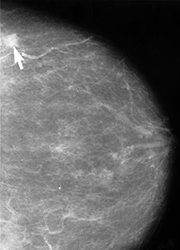

En un mamograma de película, las áreas de baja densidad, como el tejido adiposo, aparecen translúcidas (es decir, similares al fondo negro), mientras que las áreas de tejido denso, como el tejido conectivo y glandular o los tumores, aparecen más blancas en un fondo negro. En un mamograma convencional, se toma una vista lateral y superior de cada seno, aunque se pueden tomar vistas adicionales si el médico está preocupado acerca de alguna área del seno en particular.

Un radiólogo examinará cuidadosamente un mamograma para buscar áreas o tipos de tejido que se vean diferentes al tejido normal. Estas áreas podrían representar muchos tipos de anormalidades diferentes, incluyendo tumores cancerosos, masas no-cancerosas llamadas tumores benignos, fibroadenomas, o quistes complejos. Los radiólogos observan el tamaño, la forma y el contraste de una masa, así como las orillas o márgenes, que pueden indicar la posibilidad de malignidad (es decir, cáncer). También buscan pequeñas partículas de calcio, llamadas microcalcificaciones, que aparecen como puntos muy brillantes en un mamograma. Aunque por lo general son benignas, las microcalcificaciones pueden indicar ocasionalmente la presencia de un tipo específico de cáncer. Si un mamograma es anormal, el radiólogo puede ordenar vistas de mamograma adicionales, así como una magnificación o compresión adicional, y si se detectan áreas sospechosas, quizá ordenará una biopsia.